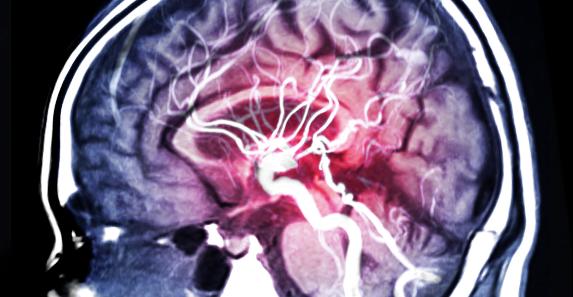

هدنا العديد من وسائل وادوات الذكاء الاصطناعي التي تم تطويرها لخدمة البشرية في المجال الطبي، وفي سياق إكمال هذه المسيرة قام باحثان بتطوير نظام ذكاء اصناعي واعد للتنبوء بنوبات الصرع بدقة عالية قبل حدوثها.

وتقوم آلية النظام الذي قاما بتطويره الباحثان هشام داوود ومجدي بيومي من جامعة لويزيانا الأمريكية على التبوء بنوبات الصرع قبل ساعة من حدوثها بدقة تصل 99.6% وأكثر، لتعطي بذلك مساحة واسعة ووقت كافي للمصابين بهذا المرض للتحكم والاستعداد للنوبات المفاجئة.

حيث أن هنالك 50 مليون شخص يعانون من نوبات الصرع حول العالم في الوقت الحالي وفقاً لاحصائيات منظمة الصحة العالمية، ليعد بذلك هذا الاكتشاف او النظام الذي مازال تحت التطوير قفزة نوعية.

مع العلم أنه هنالك العديد من الطرق الأخرى للتنبوء بنوبات الصرع عبر التخطيط الكهربي للدماغ EEG، لكن الطريقة الجديدة تقوم بالوظيفة عن طريق عملية تعتمد على استغلال تقنيات تعلم الآلة وخوارزميات تعمل على تخطيط دقيق للدماغ وتنبوء النوبات في نفس الوقت بتتبع القنوات والنواقل الكهربية في الدماغ التي تضيء أثناء النوبة.

لكن يجب الاأخذ بعين الاعتبار أن هذا النظام الجديد يحتاج مزيداً من الوقت قبل توفره للاستخدام على نطاق موسع عالمياً، حيث يعمل الفريق المطور له على تصميم رقاقة مخصصة للقيام بالعمليات الخوازمية االضرورية. على كل حال يبقى خبراً مهماً للمصابين بهذا المرض أملاً بحلول مستقبلية قادرة على معالجة النوبات الفجائية نهائياً ربما.